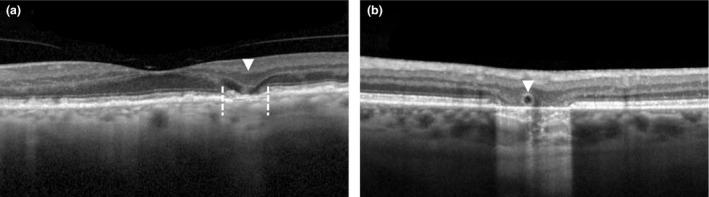

Age-related macular degeneration (AMD) is a degenerative disease of the macula, often leading to progressive vision loss. The rate of disease progression can vary among individuals and has been associated with multiple risk factors. In this review, we provide an overview of the current literature investigating phenotypic, demographic, environmental, genetic, and molecular risk factors, and propose the most consistently identified risk factors for disease progression in AMD based on these studies. Finally, we describe the potential use of these risk factors for personalised healthcare.

While phenotypic risk factors such as drusen and pigment abnormalities become more important to predict disease progression during the course of the disease, demographic, environmental, genetic and molecular risk factors are more valuable at earlier disease stages. Demographic and environmental risk factors such as age and smoking are consistently reported to be related to disease progression, while other factors such as sex, body mass index (BMI) and education are less often associated. Of all known AMD variants, variants that are most consistently reported with disease progression are rs10922109 and rs570618 in CFH, rs116503776 in C2/CFB/SKIV2L, rs3750846 in ARMS2/HTRA1 and rs2230199 in C3. However, it seems likely that other AMD variants also contribute to disease progression but to a lesser extent. Rare variants have probably a large effect on disease progression in highly affected families. Furthermore, current prediction models do not include molecular risk factors, while these factors can be measured accurately in the blood. Possible promising molecular risk factors are High-Density Lipoprotein Cholesterol (HDL-C), Docosahexaenoic acid (DHA), eicosapentaenoic acid (EPA), zeaxanthin and lutein.